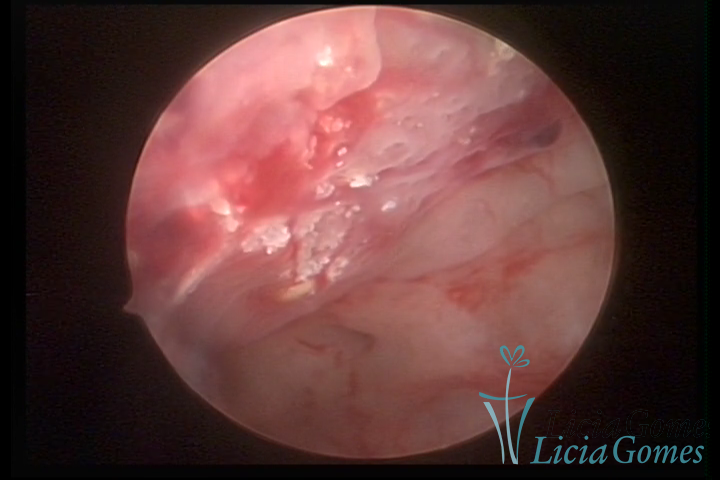

Metaplasia óssea e lesão de adenomiose

METAPLASSIA ÓSSEA